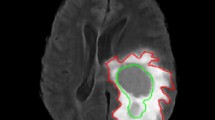

Thresholding techniques for image segmentation is one of the most popular approaches in Computational Vision systems. Recently, M. Albuquerque has proposed a thresholding method (Albuquerque et al. in Pattern Recognit Lett 25:1059–1065, 2004) based on the Tsallis entropy, which is a generalization of the traditional Shannon entropy through the introduction of an entropic parameter q. However, the solution may be very dependent on the q value and the development of an automatic approach to compute a suitable value for q remains also an open problem. In this paper, we propose a generalization of the Tsallis theory in order to improve the non-extensive segmentation method. Specifically, we work out over a suitable property of Tsallis theory, named the pseudo-additive property, which states the formalism to compute the whole entropy from two probability distributions given an unique q value. Our idea is to use the original M. Albuquerque’s algorithm to compute an initial threshold and then update the q value using the ratio of the areas observed in the image histogram for the background and foreground. The proposed technique is less sensitive to the q value and overcomes the M. Albuquerque and k-means algorithms, as we will demonstrate for both ultrasound breast cancer images and synthetic data.